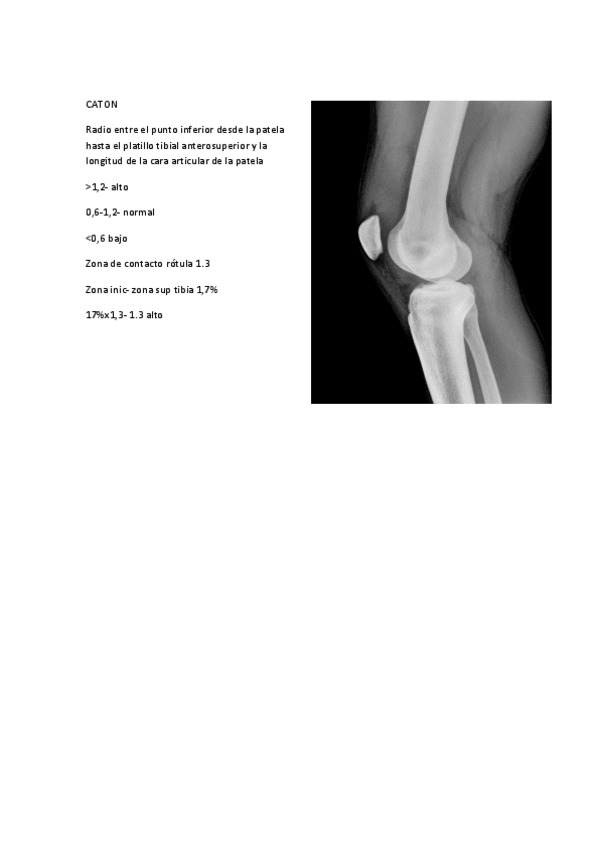

He publicado nuevos ejercicios de 3º Podología Deportiva: IMAGENES-PARA-GONIOMETRIA-DE-LA-RODILLA.pdf